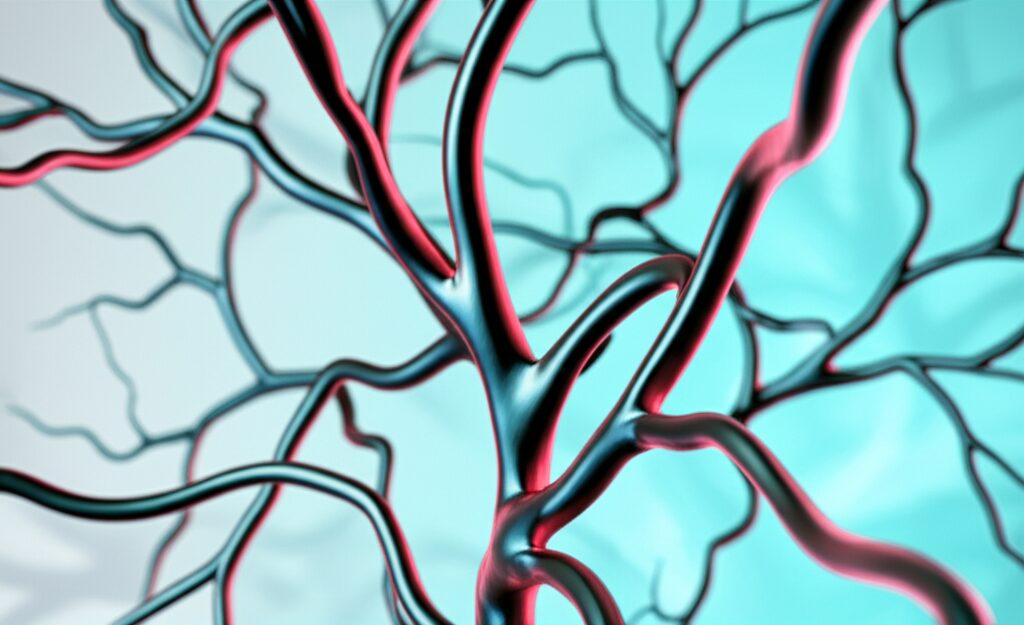

2대질환 진단비보험은 보통 암과 뇌·심장질환(뇌혈관/허혈성 심장질환)을 중심으로 진단 시 목돈을 주는 구조입니다.